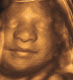

A pregnancy ultrasound is one of the most basic tests that are conducted after initial confirmation of the pregnancy. An ultrasound is conducted at normal intervals for determining the position and growth of the baby. It is generally utilized by the doctors for getting an accurate picture of a mother's pregnancy. Use of 3D pregnancy ultrasound is an extremely useful tool for diagnosis of the fetus in the mother's womb. In some of the countries, a routine ultrasound scanning is performed for identifying the potential defects of the baby before birth.

The recurring beams of the ultrasound scan the baby and go back to the transducer. The data obtained from the different reflections recomposes in the form of a picture on display screen. The gender of the child can normally be identified after 15 weeks of pregnancy but it largely depends upon the operators' aptitude and performance of the sonographic machine. Movements like fetal heartbeats and any possible malformations can be identified and essential measurements can also be accurately made based on the pictures displayed upon the monitor screen. 3D pregnancy ultrasound can also be helpful in identifying any structural abnormalities of the fetus.

During the first trimester of a pregnancy, these ultrasounds are conducted for checking the status of the woman's cervix, gestational sac, uterus, embryo and any other deep structures of the pelvic area. The 3D pregnancy ultrasound conducted during the 2nd and 3rd trimester is meant for getting a clear picture of the placenta and the fetus as well as for providing details about growth and position of the baby.